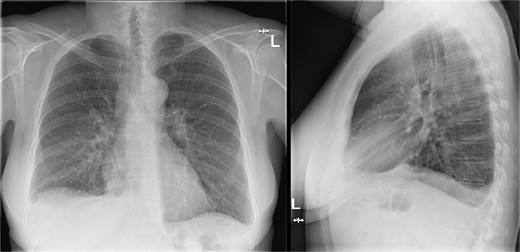

Additional imaging diagnostics with X-ray demonstrated bilateral pleural effusion, more apparent at the right side (Fig. 1). A subsequent computed tomography (CT) scan showed no signs of pulmonary embolism and confirmed the pleural effusion (Fig. 2). In addition, air was seen in the anterior mediastinum (pneumomediastinum). Both air and pleural effusion were attributed to normal healing after the recent VAMLA, and in the absence of clinical alarm symptoms the patient was sent home. In the absence of loculation or contrast captation, the bilateral pleural effusion had no radiological signs of empyema. One of the symptoms of pleural effusion is dyspnea which was also present in the patient. In addition, there was no suspicion of an infectious cause with normal vital values with a temperature of 37.7°C and no significant elevation of WBC or CRP. It was suspected that the effusion was postoperative or reactive to the suspected lung cancer. Regarding the hoarseness, the most likely cause was post-operative swelling of the surgical area. As the hoarseness did not occur immediately post-operative, iatrogenic recurrent nerve injury was not suspected.

Chest X-ray during visit to the emergency department showing bilateral pleural effusion.